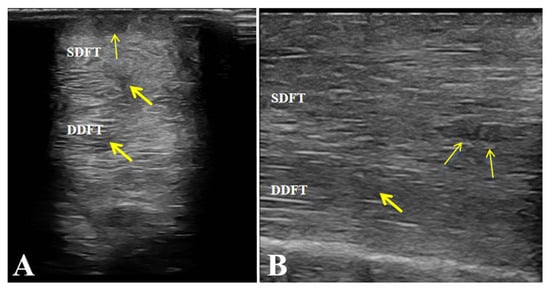

After completing the medication combined with LIPUS-assisted therapy, ultrasonographic examination revealed marked improvement in the overall echogenicity of the affected SDFT and DDFT. Both tendons exhibited uniformly increased echogenicity, with no diffuse hypoechoic areas or regions of heterogeneous echotexture within the tendon substance. The internal homogeneity had become comparable to that of the contralateral healthy tendons. In the sagittal scans, the normal parallel, fibrillar echotexture was largely restored, showing well-organized, continuous fibers aligned with the longitudinal axis of the tendon, without evidence of disruption or fiber-pattern irregularity (Figure 6).

Figure 6. Post-treatment ultrasonographic images of the affected horse. (A,B) Increased echogenicity and uniform fibrillar alignment of the superficial digital flexor tendon (SDFT) and deep digital flexor tendon (DDFT), without fibrosis or adhesions. Arrows indicate the repaired areas of the tendon post-treatment.